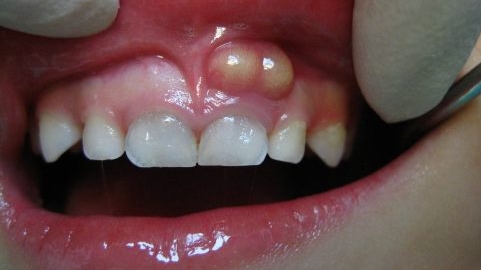

A dental abscess is a painful infection that occurs in the tooth or the surrounding tissue. It is usually caused by bacterial infection that enters through a cavity, cracked tooth, or gum disease. The infection leads to the formation of a pus-filled pocket, which can cause extreme pain and discomfort. If left untreated, a dental abscess can lead to various complications. It is important to understand and recognize these complications in order to seek timely treatment.

There are two main types of dental abscesses: periapical abscess and periodontal abscess. A periapical abscess occurs at the tip of the tooth’s root, while a periodontal abscess occurs in the gums next to the tooth. Both types can lead to similar complications if not properly treated.

In some cases, a dental abscess can lead to soft tissue infections in the surrounding areas. This can cause pain, swelling, and discomfort. Prompt treatment is necessary to prevent the infection from spreading further. -